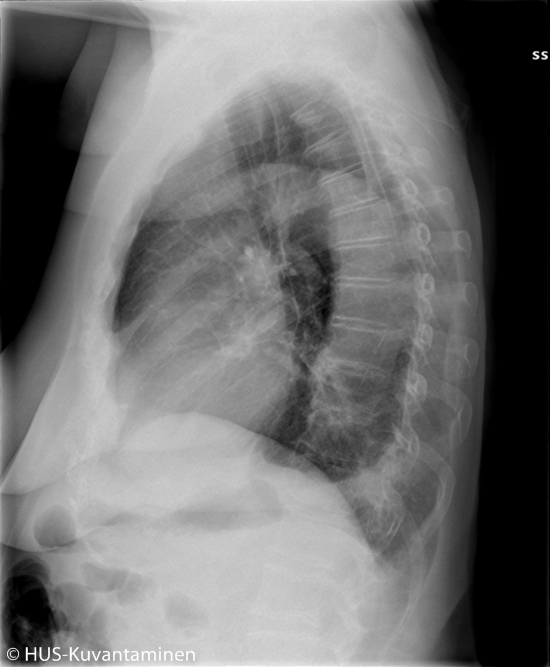

Aortan dissekoituma keuhkokuvassa (sivukuva ilman löydösmerkintöjä).

Keski-ikäinen nainen tuli vastaanotolle yhtäkkiä alkaneen terävän selkäkivun vuoksi. Verenpaine oli koholla.